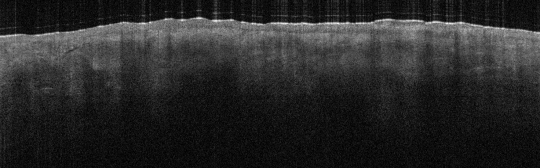

VA1: Left Forearm, Actinic Keratosis

VA1: Right Forearm, Normal